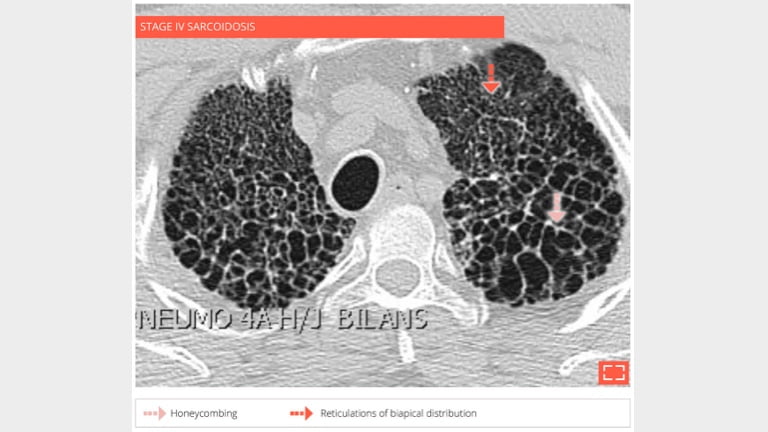

4. Honeycombing

honey-4

56-year-old man with history of sarcoidosis. Typical honeycombing in a upper lobe distribution.